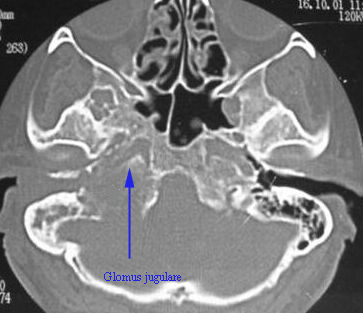

Investigations: Radiological investigations help in the diagnosis.

CT scan and Contrast MRI using Gadolinum enhancement is very helpful in delineating tumor extension.

CT scan image of a patient with Glomus jugulare